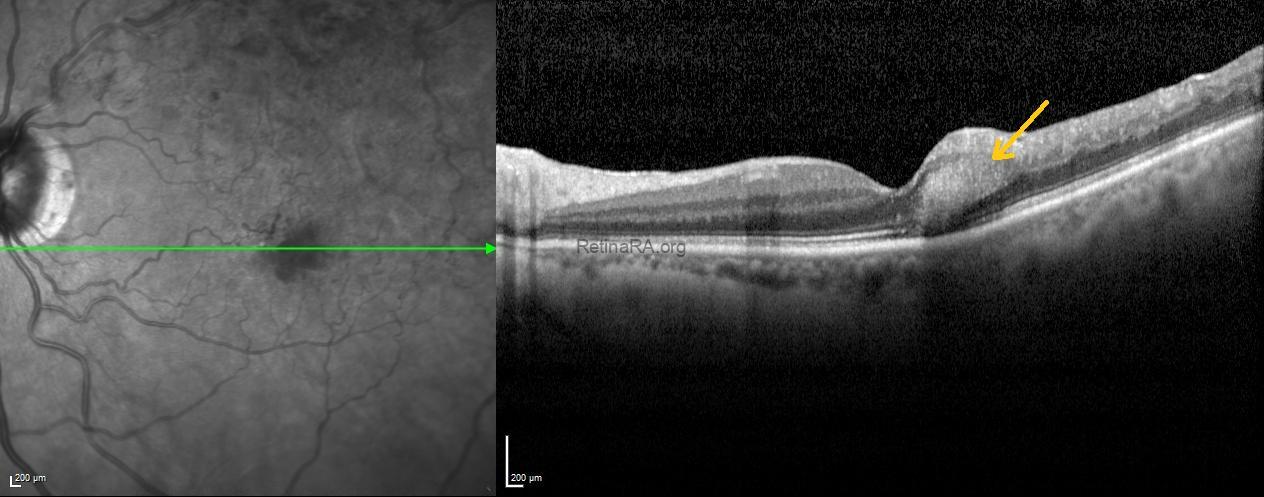

Optical coherence tomography scans passing through the feathery hemorrhages revealed obliquely oriented hemorrhages with shadowing within the Henle fiber layer at the temporal fovea (indicated by arrows).

These findings were consistent with a Henle fiber layer hemorrhage associated with branch retinal vein occlusion. The patient was monitored for spontaneous resolution, with follow-up OCT and FFA planned to assess ischemia and collateral vessel progression.

Henle fiber layer hemorrhage is a distinct type of deep intraretinal hemorrhage localized in the macula, following the oblique orientation of Henle fibers. On fundus examination, it often appears feathery or petaloid, radiating from the fovea, while OCT shows hyperreflective lesions with shadowing in the Henle fiber layer. These hemorrhages are usually associated with vascular disturbances in the deep capillary plexus. Although they can occur in various retinal vascular conditions, Henle fiber layer hemorrhages may also be seen in eyes with branch or central retinal vein occlusion. Recognizing this pattern is important for accurate diagnosis and management.